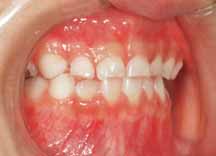

3.下顎前突(受け口) 下の歯が上の歯より出ています

治療前

上の八重歯が並んだ状態です

治療後